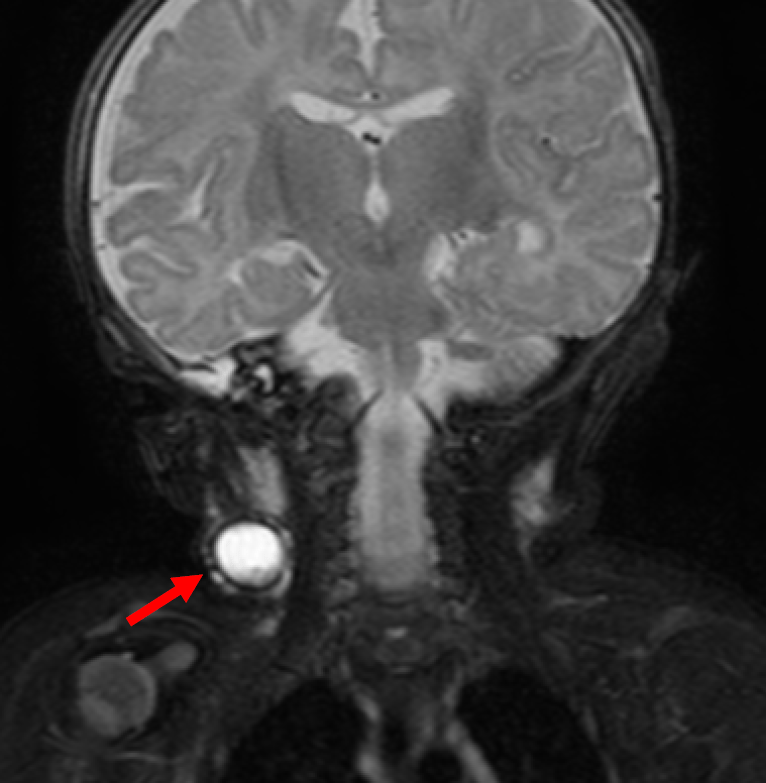

The infrahyoid neck. This mri study of brain shows. Multiple intra axial round to ovoid unilocular cystic signal intensity focal lesions in supra tentorium as well as posterior fossa. A handbook to seek information on pediatric surgery related topics.